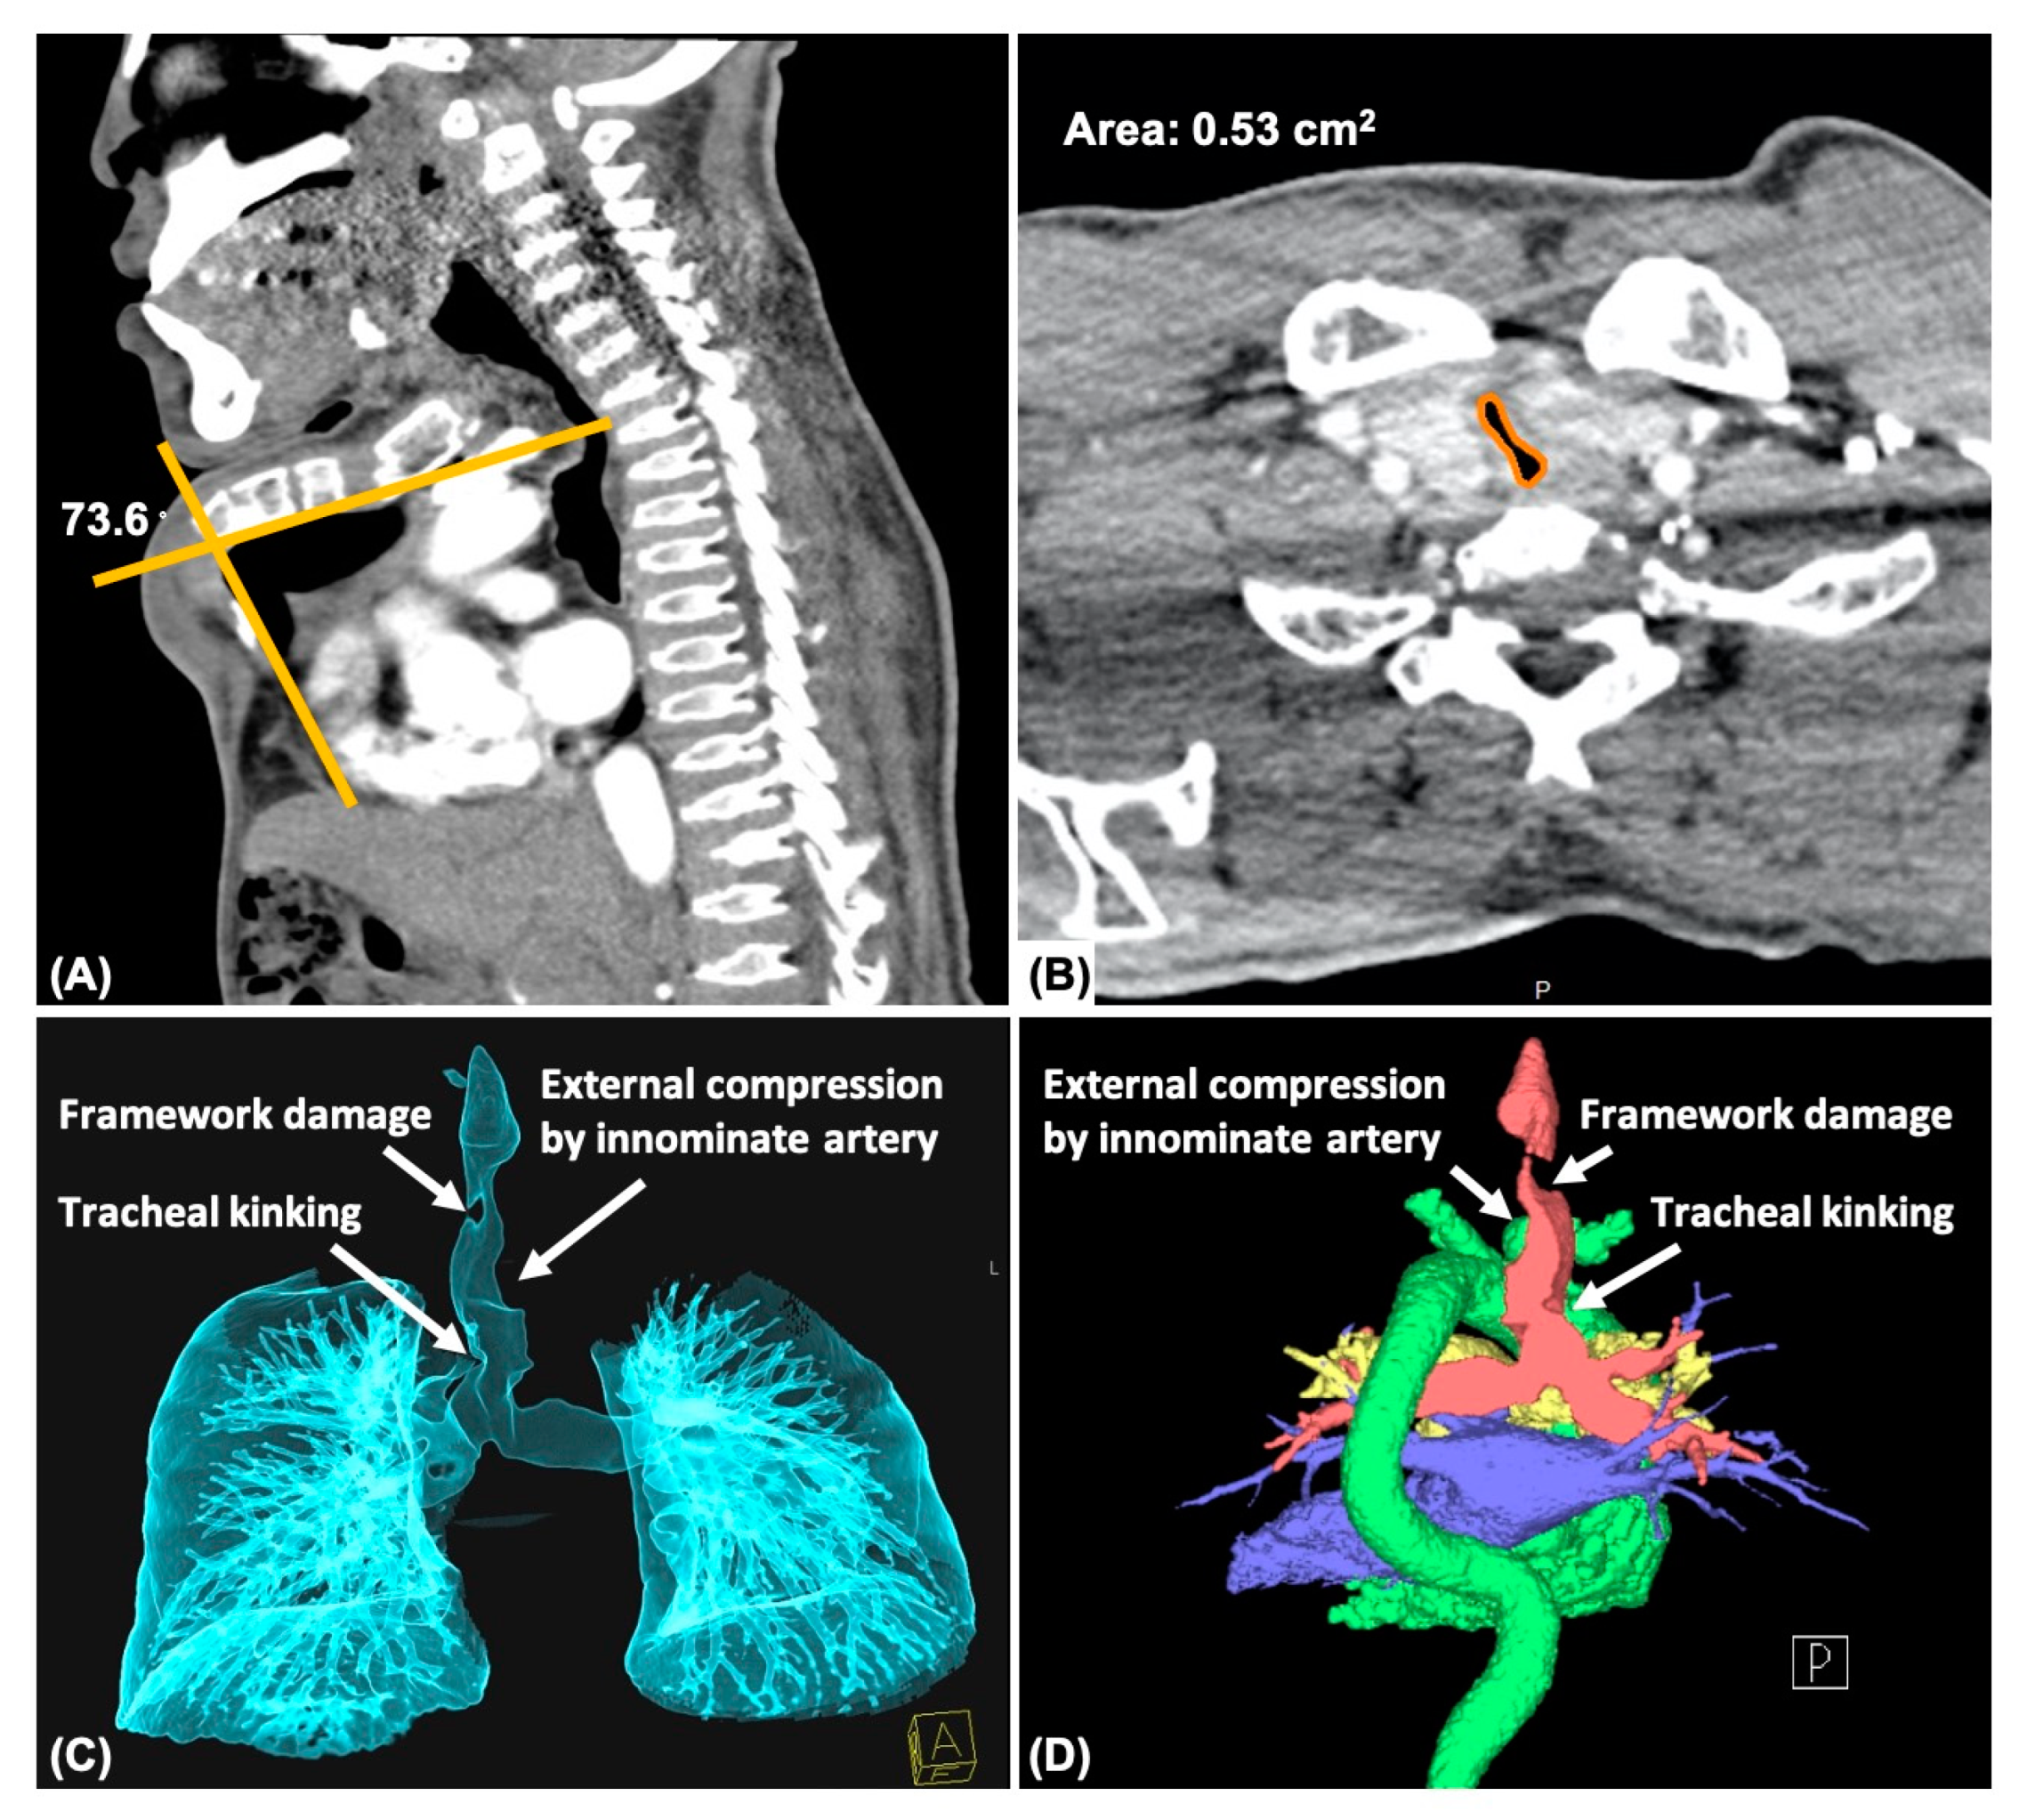

| Sternum angle (°) | 103 · | 89.2 | 107 | 85 | 162 | 127 | 134 | 89 | 120 | 73.6 | 125 | 44 | 142 | ||||

| Trachea | Collapse | – | ++ | + | ++ | + | + | ++ | +++ | +++ | +++ | – | + | ++ | |||

| NW ratio | 68% | 47% | 61% | 37% | 53% | 51% | 27% | 9% | 22% | 16% | 67% | 57% | 37% | ||||

| Torsion | – | – | + | + | – | – | + | - | + | + | – | + | + | ||||

| Kinking | – | + | – | – | – | – | – | – | – | + | – | + | – | ||||

| External compression | – | + (I+A) | + (I) | + (I) | – | – | + (I+A) | + (I) | + (I) | + (I+A) | – | – | + (I) | ||||

| Framework damage | – | – | + | – | – | – | – | – | – | + | – | – | + | ||||